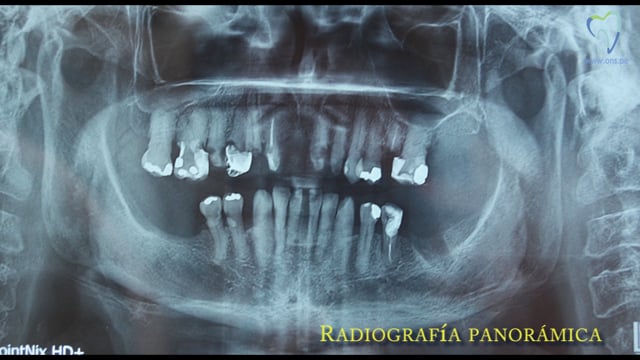

Una paciente había sido tratada con cinco implantes en la maxila anterior. La pérdida de un incisivo lateral adicional debido a una enfermedad periodontal avanzada hizo que se añadiera un implante post exodoncia antes de iniciar la elaboración de la prótesis fija sobre implantes.